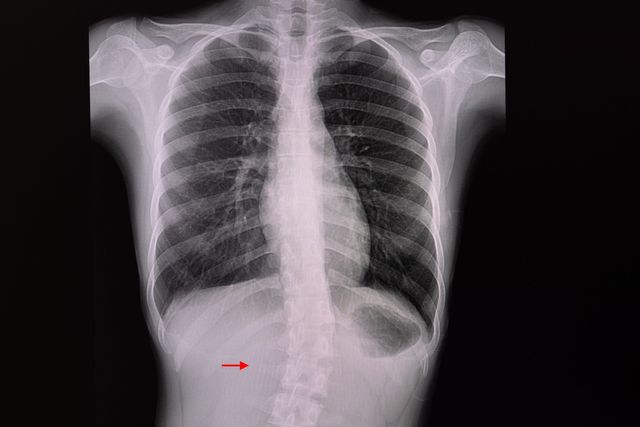

정상적인 척추는 정면에서 봤을 때 일직선이고, 옆에서 봤을 땐 경추와 요추는 앞으로 휘고(전만곡), 흉추와 천추부는 뒤로 휘어(후만곡) 있다. 척추측만증은 척추를 정면에서 봤을 때 옆으로 휜 것을 지칭하지만, 실제로는 단순한 2차원적인 기형이 아니라 추체 자체의 회전 변형과 동반돼 옆에서 봤을 때도 정상적인 만곡 상태가 아닌 3차원적인 기형 상태를 말한다.